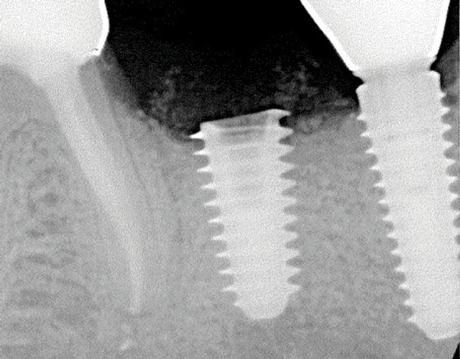

Implants with internal hex connections are more prone to failure at the connection than those with external hex connections.28 This is related to the thickness of the metal at the thinnest point between the internal surface of the interface and the external surface at the crestal area of the implant. When overloaded, implants with an internal hex connection may present with fractures at the points of the hex.29 These points are where the metal is the thinnest at the crestal portion of the implant and where stress is concentrated during overloading. This is less problematic in wider diameter implants because the metal is thicker in this area of the implant; however, in standard or narrow diameter implants, fracture may result, causing catastrophic failure of the implant (Figure 1). This may also occur in other internal implant connection types, such as trilobe connections, especially when the crestal thickness of the implant is minimal, leading to fracture of the coronal aspect of the implant (Figure 2). Implants with conical connections are not immune to potential fracture in this area, and the thin walls of some standard or narrow diameter models may split even without the isolated stress points observed in internal hex-, trilobe-, and octagon-type connections (Figure 3).30 Sometimes, fractures of implants at the coronal aspect are not clinically visible but, instead, are identified radiographically either after a patient complaint of pain in the area, due to the presence of soft-tissue inflammation, or during a routine examination with no patient complaint (Figure 4).

(1.) Fractures at the points of the internal hex connection where the metal is thinnest resulting in catastrophic implant failure.

Figure 1